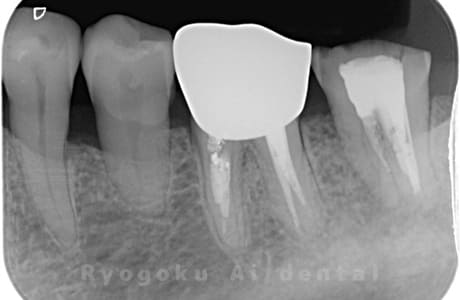

Case12

-

- 原因

- 右上5番歯根破折

- 治療内容

- インプラント治療

- 治療費用

- 約600,000円

左上に違和感があるとのことでご来院された患者様です。歯が割れているため、抜歯と診断し、即時でインプラント埋入を行いました。大変ご満足して頂けました。

<リスク・副作用>

治療後、痛みや違和感、出血、腫れなどが出る事があります。喫煙者、糖尿病などの方の場合、歯が生着しない場合があります。